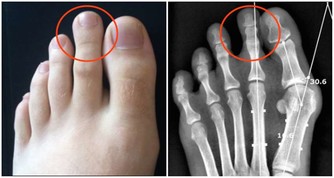

而油膩食物吃多了,其中所含的膽固醇過高,又會影響膽汁酸、膽固醇、卵磷脂、鈣鹽的平衡,容易患膽結石。